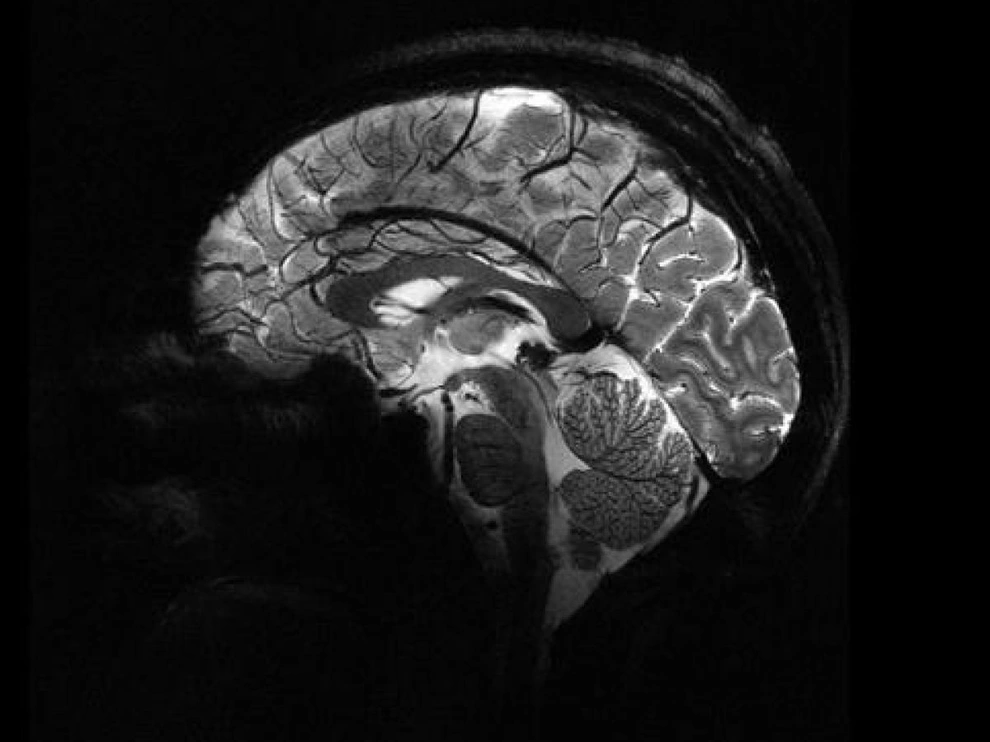

| Bộ não người chụp từ máy quét MRI Iseult (Ảnh: CEA). |

Những hình ảnh lịch sử này được chụp từ máy quét MRI Iseult, chụp cộng hưởng từ, trong trung tâm nghiên cứu CEA, Ủy ban Năng lượng Nguyên tử Pháp.

Với những hình ảnh này, chúng ta có thể thấy những chi tiết khá ngoạn mục. Nó cho chúng ta biết về các chi tiết giải phẫu như tĩnh mạch hoặc các lớp vỏ não mà trước đây không thể đạt được".

Nhờ máy quét MRI Iseult, các nhà nghiên cứu có thể bóc tách bộ não của chúng ta với độ chính xác đáng kinh ngạc: khoảng một phần trăm triệu mét hay độ dày của bốn sợi tóc.